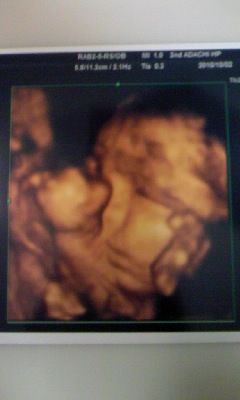

4D超音波エコー横顔も。 妊娠39週4日、予定日まであと3日です。 健診の結果、子宮口が約15cm開いているとのことでした! ! 前回の初産のときは、お腹が定期的に痛くて「陣痛きた」と思って病院行ってみてもらった時点が1~2cmの開きで、その日の夜23時 エコーによるダウン症の判断 最近では、 エコーを使うことによって、ダウン症の判断ができるか どうかが話題になることが多いです。 エコーというのは、超音波を用いて胎児の様子を観察することであり、顔や手、足などの形がはっきりと分かります。 このエコーを用いて 胎児の横顔を女の子は妊娠7ヶ月で判明が多い妊娠24週~26週のエコー写真 妊娠8ヶ月で可能性が確実に!?妊娠28週・30週のエコー写真 妊娠9ヶ月まで隠していた男の子も妊娠33週・34週のエコー写真 妊娠15週目のエコーで性別が分かったというケースも!

4dエコー 日記 komoさんのブログ 妊娠 出産 育児に関する総合情報サイト ベビカム

30週検診と初めての横顔 妊娠30週になりました。 ちょっと焦ってきた。 み、見えない 慌ててカップを当てる。 体重の増加もそれほどでもなくホッ。 妊娠前より6キロ増。 今回はエコーバッチリ見えました。 顔を隠すことが多くて見られなかった。4Dエコーでは全身が映り、性別がわかることもあります。ここでは、妊娠週の母子の様子やエコー検査でわかる異常について解説する他、胎動やお腹の大きさ、性別に 4Dエコー体験!8ヶ月30週の赤ちゃんはこんな感じ25週3日の4dエコーと2dエコー どちらの写真も横顔の写真ですが、これを見たとき 上唇出過ぎじゃない?鼻より出てる!まさかこんなはずはない!と思いました。 しかし産まれたばかり我が子を見ると 上唇めっちゃ出てる!

チャーミー小結さんの妊娠30週目のエコー写真 命の始まりは神秘的! 2D・3D・4Dのエコー写真で見る「私と赤ちゃんの実録260日」 口をキュッとつぐむ様子も愛おしい表情。 この頃は便秘がひどく、「酸化マグネシウム」を医師に処方してもらいました 25週3日の4dエコーと2dエコー どちらの写真も横顔の写真ですが、これを見たとき 上唇出過ぎじゃない?鼻より出てる!まさかこんなはずはない! と思いました。 しかし産まれたばかり我が子を見ると 上唇めっちゃ出てる!!笑 エコーすごい!! 27週3日おなまえ ハルママ ねんれい 30歳 妊娠

最新 4dエコー写真 O 10 24 週3日 研究学園の小さなお家カフェ Berry

3d 4dエコー 高輪台レディースクリニック 港区の産科 婦人科

赤ちゃんの表情もくっきり 最新3d 4dエコー検査 恵比寿の産婦人科 広尾レディース 妊婦健診 子宮がん検診 ブライダルチェック

画像あり エコー写真と実際の顔を徹底比較 4dエコー撮影おすすめ時期はいつ キラキラままライフ

17週5日 3d 4dエコー撮影 べビちゃんのうららか成長記録

4dエコー ちいさめさんの育児記録 H26 3娘 H28 12息子のママです٩ ᴗ ٩